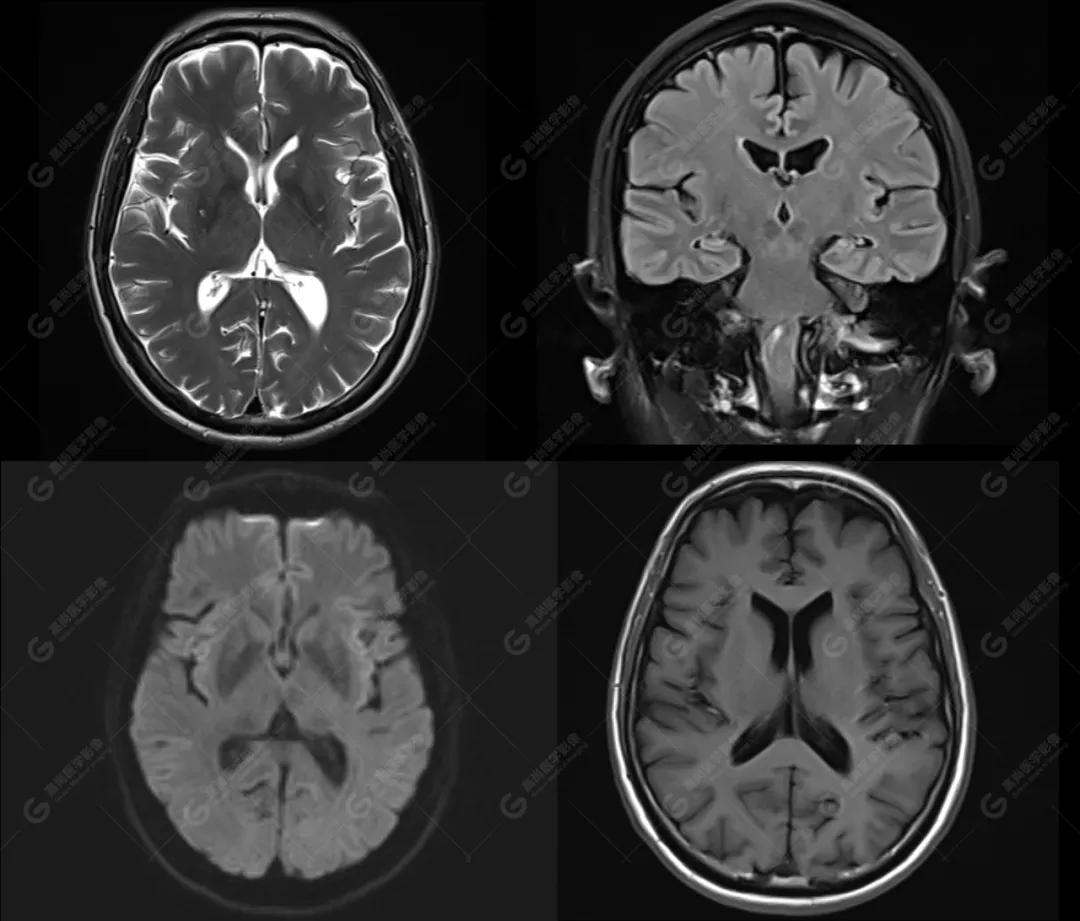

磁共振影像图

图1

影像诊断: 1、颅脑MR平扫未见明显异常。

2、C3/4、C4/5 椎间盘向后中央突出 、C5/6、C6/7 椎间盘膨出 , 相应平面蛛网膜下腔受压, C5/6、C6/7水平 右侧神经根出口稍变窄 ;颈椎右侧上部神经根袖区少许T2高信号,请结合临床。

3、颈椎退行性改变。4、双侧上颌窦粘膜下囊肿。